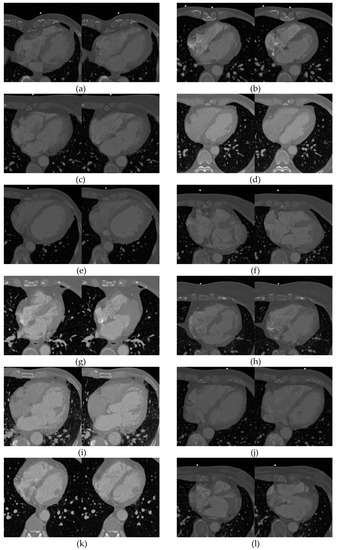

4.4. Registration of 3D Cardiac CT Image